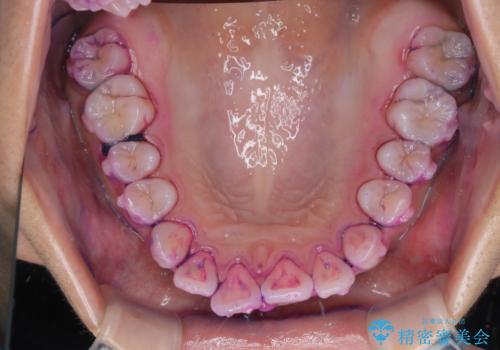

染め出し液を使ってプラークを染め出すことにより、普段の歯みがきで磨き残している場所を目で確かめることができます。

日々の歯磨きを上達するには、まずどこが磨けていないか認識することが大切です。